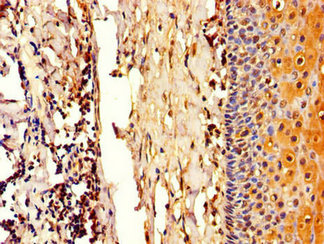

Immunohistochemistry of paraffin-embedded human tonsil tissue using CSB-PA896912LA01HU at dilution of 1:100